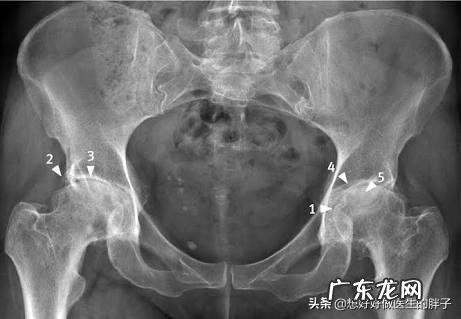

其实很多的髋关节疼痛往往并不是由于股骨头坏死导致的,常见的引起髋关节疼痛的原因有髋关节的滑膜炎症、髋关节骨关节炎以及髋关节的撞击综合征,这几种种疾病发生的几率比股骨头坏死要多很多,而是否需要口服氨糖,还是需要根据患者的病情来决定 。

髋关节骨关节炎很多人听说过膝关节、肩关节的骨性关节炎,但是对于髋关节的骨性关节炎并不是特别的了解 。其实在髋关节骨性关节炎的病变也是比较常见的,它的发病原理和其他部位的骨性关节炎机理是一样的,都是髋关节软骨的退变 。

当髋关节骨性关节炎发展到晚期,其x光表现与股骨头坏死非常的相像,所以也造成了临床上大量的误诊 。

在髋关节骨关节炎发病的早期,大家可以做髋关节的核磁,明确是否存在股骨头的缺血 。排除是股骨头坏死的可能,在髋关节的周围可以发现有软骨的磨损以及骨赘的形成,那么就证明是髋关节的骨关节炎导致患者出现髋部的疼痛以及逐渐的活动受限 。

如果是髋关节骨关节炎的早期是可以口服氨糖这一类的药物来控制病情的,但是疗效并不是非常确切,如同膝关节等关节的骨性关节炎一样,有效率可能仅仅在50%左右 。其实也就是说,口服氨糖缓解髋关节骨关节炎的症状可能性在一半一半 。当髋关节骨性关节炎发展到晚期,也会出现软骨下骨的严重的硬化,患者会表现出剧烈的髋关节疼痛以及活动的功能障碍 。